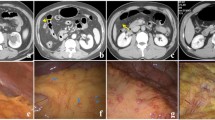

In this retrospective study, we included 49 patients with occult PM and 49 control patients (without PM) who underwent preoperative CT and subsequent surgery between January 2016 and December 2018. Clinical information and CT semantic features were collected, and CT radiomics features were extracted. A predictive clinical-CT model was created using multivariate logistic regression. The least absolute shrinkage and selection operator algorithm and logistic regression were used for constructing 2D and 3D radiomics models. These models were validated with an external cohort (n = 30). Receiver operating characteristics curve with area under the curve (AUC), sensitivity, and specificity were used to evaluate predictive performance.

Tumor size, mild ascites, and serum CA125 were independent factors predictive of occult PM. The clinical-CT model of these independent factors showed better diagnostic performance than 2D and 3D radiomics models. In the external validation cohort, the AUCs of different models were as follows—clinical-CT model: 0.853 (sensitivity, 66.7%; specificity, 93.3%); 2D radiomics model: 0.622 (sensitivity, 80.0%; specificity, 46.7%); and 3D radiomics model: 0.676 (sensitivity, 60.0%; specificity, 86.0%). The clinical-CT model nomogram showed good clinical predictive efficiency to assess occult PM.